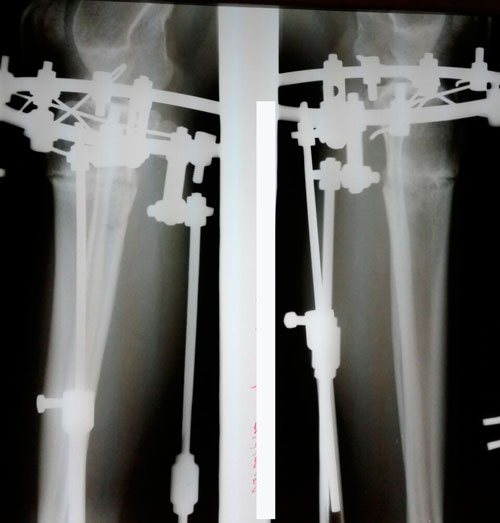

рентген и фото ножек, через 2 месяца с момента снятия аппаратов.

Сращение отличное, разрешено обувать каблучки, привыкайте к красивому!

Физические нагрузки разрешены (спорт) постепенно, по нарастающей.